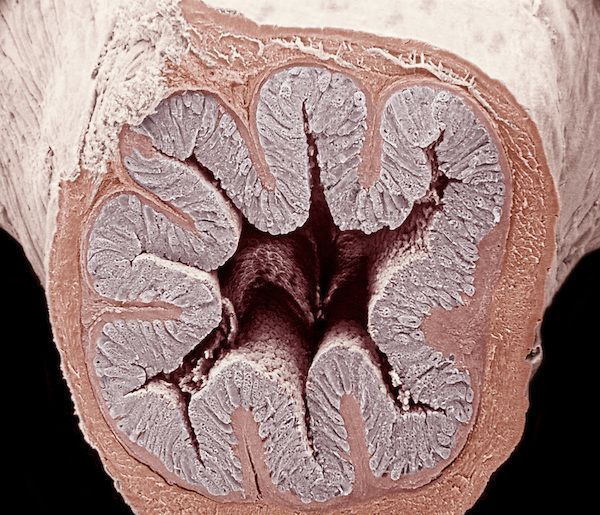

我们这里会详细讲述黏膜上皮:人体吸收营养物质的奥秘就来自于这些“毛绒绒”的东西。如果把小肠切开铺平来看,它们就像绒毛地毯一样。

绒毛和微绒毛

肠道黏膜上皮细胞并不是平坦的,它们实际上组成了一个一个突出于肠腔的结构,叫绒毛。每一个绒毛都会有数千个肠道细胞组合而成,里面有负责提供营养成分的血管。

新形成的肠细胞从陷窝开始迁移时,开始在顶端形成刷状缘,刷状缘叫微绒毛,直径0.1微米,长度1微米。每一个细胞有大约36000根微绒毛,可以将表面积增加10-20倍,可以非常显著的增加肠道对食物的吸收。这就是我前面提到的肠道吸收的秘密。

实际上,整个肠道上皮的可吸收面积比本来的肠道面积要高几百倍,绒毛和微绒毛这些结构带来的表面积扩张使小肠内表面面积可以达到200m²,相当于标准篮球场的一半大小,大大地增加了可吸收面积。